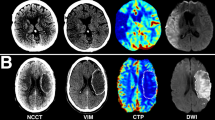

Anonymized CT imaging data was segmented using semiautomatic commercially available software (Analyze 11.0, Biomedical Imaging Resource, Mayo Clinic, Rochester, MN). The raters (RM, SE) were blinded for all other imaging data and patient information. CTP-guided delineation of ischemic lesion NWU on admission imaging was determined according to recently published methods11,13. In brief, the visually evident, circumscribable hypoattenuated ischemic core lesion on NCCT was assessed by densitometric measurements (Dischemic). A corresponding region of interest was mirrored symmetrically on the contralateral, non-affected hemisphere (Dnormal). In cases where early hypoattenuation was not visibly evident, the CTP-generated CBV map was used as a visual guide for the selection of the region of interest (ROI). ROI histograms were sampled between 20 and 80 Hounsfield units (HU) to exclude voxels that correspond to cerebrospinal fluid or calcifications. The density measurements, Dinfarct and Dnormal, were then used to calculate percent NWU (%NWU, Eq. 1), i.e., the proportion of water uptake within the infarct lesion compared to the contralateral side.

Examples of patients with high (A–C) and low (D–F) NWU and their association with pCore overestimation. Both patients presented within a similar time frame and achieved near-completed reperfusion. (A, D: admission imaging; B, E: rCBF < 20% CTP maps; C, F: follow-up imaging). NWU net water uptake; pCore rCBF20%-defined core at admission; CTP CT perfusion.